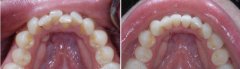

孩子前牙拥挤有危害吗?

前牙拥挤在牙颌畸形中是较为常见的。前牙拥挤的原因主要是颌骨前部发育不足...【详细】